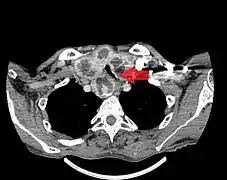

- Goitre comprimant la trachée cervicale.

Rétrécissement trachéal (flèche rouge). Tomodensitométrie (coupe transversale).